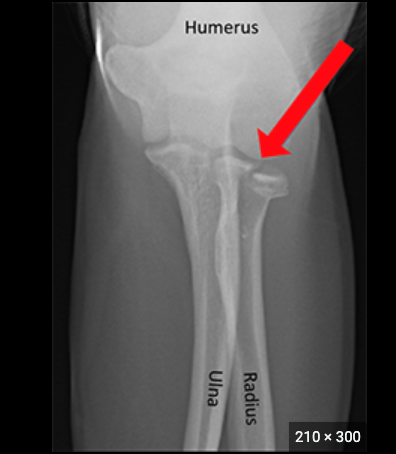

elbow joint

Bones that articulate:radius, ulna

Joint type: hinged joint

Actions: moves in one plane up and down